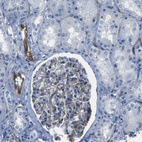

Immunohistochemical staining of human kidney shows moderate cytoplasmic positivity in cells in glomeruli.